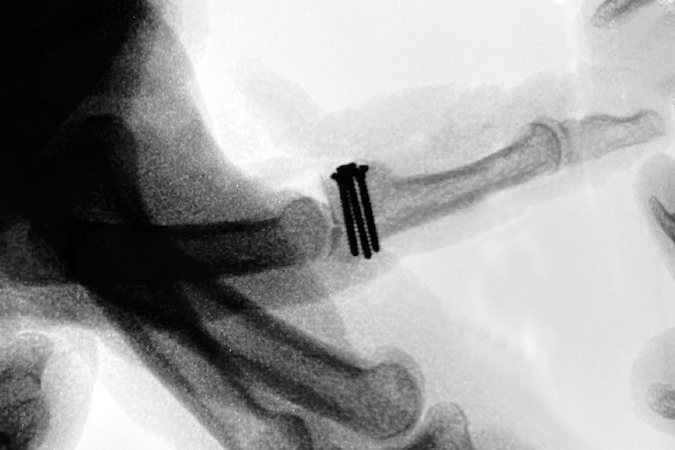

- if the injury leads to PIP joint instability, dorsal fracture-dislocations typically require surgery such as (ORIF) or hemihamate arthroplasty. The hemi-handmade arthroplasty is excellent option for treating unstable comminuted dorsal PIP joint fracture-dislocations. This procedure is usually indicated when 50% or more of the volar middle phalanx is fractured, thus producing an unstable dislocation. This procedure was first described by Hastings at the 1999 American Society for Surgery the Hand annual meeting. This procedure is done through a volar approach to the PIP joint. A “V” or zigzag incision is made in the skin, the flaps mobilized, the neurovascular structures identified and protected, and the flexor tendon sheath visualized. The A3 pulley is opened, if not already opened by the injury. The A2 and A4 pulleys are preserved. The flexor tendons are retracted exposing the volar plate and more distally the volar fracture in the middle phalanx. This is followed by releasing the attachments of the volar plate to the accessory collateral ligaments. This release allows the volar plate to be folded back proximally, thus exposing the rest of the middle phalanx fracture site. Fragments of bone and articular surface that are attached to the plate are removed. Next, the collateral ligaments are released, and the joint is hyperextended into the “shotgun” position. The defect in the volar middle phalanx’s articular surface is assessed. A rongeur or small saw is used to shape the defect so that it can accommodate a block-shaped osteochondral graft. The defect’s size is measured carefully. The joint is temporary reduced and attention turned to the donor site of the ipsilateral ring, little and hamate joint. After carefully locating the joint, a dorsal incision is made to expose the joint while simultaneously protecting the extensor tendon and the dorsal ulnar sensory nerve. At the ring, little, and hamate joint level the periosteal and capsular flaps are raised to allow visualization of the joint and the dorsal hamate. Next, a block-shaped graft centered on the apex of the hamate at the joint between the ring and little metacarpals is marked and carefully measured. The block graph should be slightly larger than the measured defect in the base of the middle phalanx. The longitudinal hamate cuts are made first. The proximal transfer osteotomy in the hamate is then performed. The final cut is made with the appropriately sized curved osteotome. Some surgeons start proximally through a notch in the proximal hamate, while other surgeons start distally with or without removing a portion of the ring and little metacarpal bases. Do not make the graph too thin, do not fragment the graft, and do not damage the articular surface of the hamate or the metacarpals. Once harvested, the block graft is brought to the finger and placed in the middle phalanx defect. It is temporarily held in place with a small K-wire. The surgeon should align the articular surface anatomically and tilt the graft to assure a cup -shaped surface of the middle phalanx base as visualized from the lateral aspect of the PIP joint. Note, the cartilage of the hamate is often thicker than the cartilage of the middle phalanx which may affect the appearance of the PIP joint on X-Ray. On occasion, adding extra cancellous bone graft from the hamate is needed distally in order to provide the proper tilt of the block-shaped graft and facilitating the curved laterally visualized cup shape of the base of the middle phalanx. Note, morphologic studies have shown this graft is not a perfect match to the volar middle phalanx base but typically variations have not affected the clinical outcome. Secure the graft with two or three 0.9 two 1.5 mm screws through the graft and into the dorsal middle phalanx dorsal cortex. Remove the K wire. Reduce the joint and reattach the volar plate to the stumps of the collateral ligaments left on the base of the middle phalanx. Check the range of motion and the stability. Close the wrist and finger incisions. Splint the PIP joint in 15 to 20 degrees of flexion. Start post-operative range of motion exercises at 7 to 10 days.23-27 For more information on hemihamate arthroplasty see the surgical images below and the links to HAND.E.

- ORIF with an autologous hemihamate osteoarticular graft may be required for PIP fracture-dislocations in which more than 50% of the base of the middle phalanx is fractured with an intact dorsal cortex.10

- The hemi-hamate autograft and screw fixation procedure has been associated with satisfactory results in 13 patients with PIP joint fracture-dislocations.10